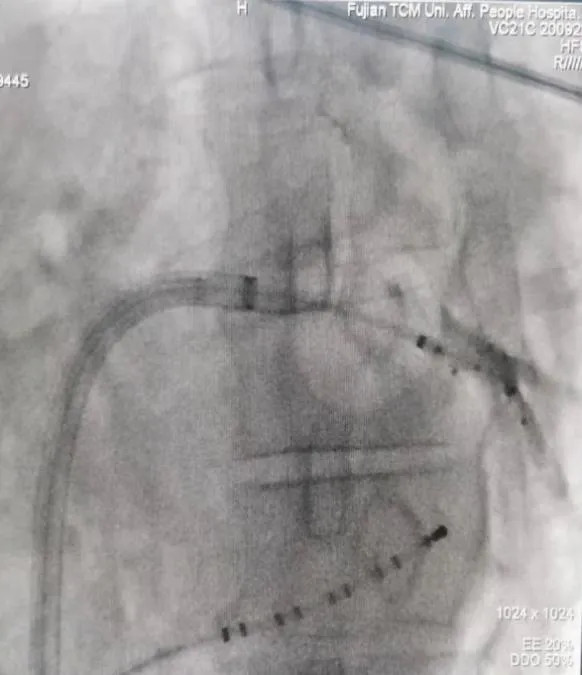

射频消融术

三维电生理系统支持下的房性心动过速射频消融术

三维电生理系统支持下的心房颤动+心房扑动射频消融术

长程持续性房颤射频消融术(环肺静脉隔离+顶部线消融)